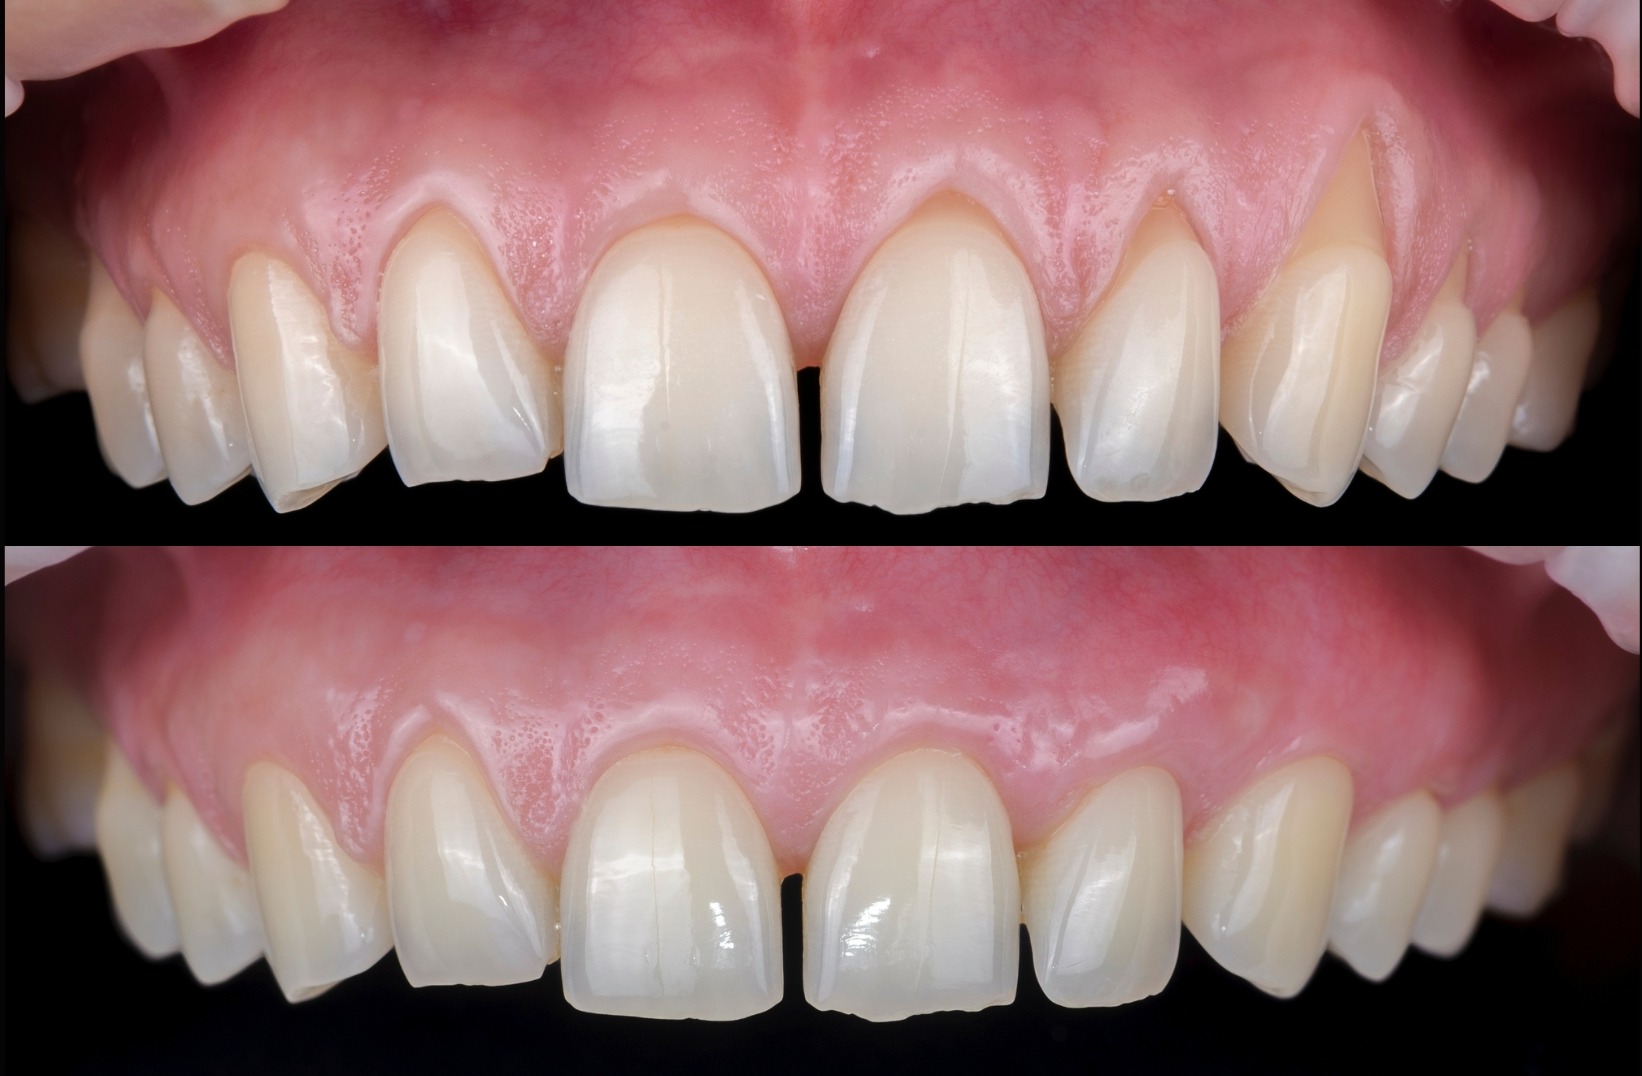

Recession Coverage Maxillary Teeth

Aesthetic concerns, hypersensitivity, cleaning ease. All resolved with mucogingival surgery!